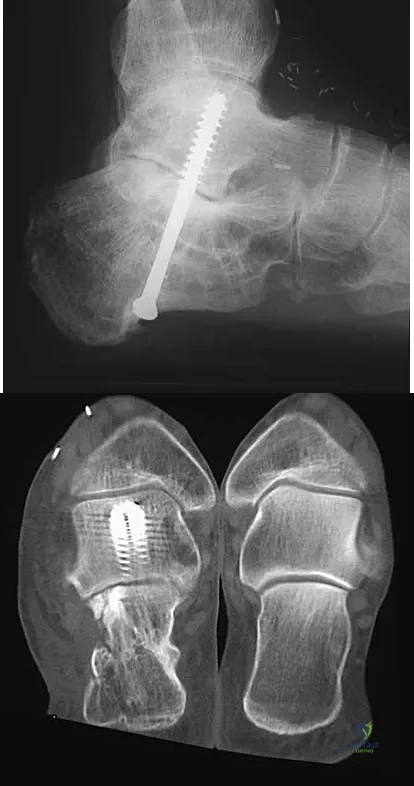

A 45-year-old man has persistent hindfoot pain that is aggravated by weight-bearing activities. History reveals that he sustained a calcaneus fracture 2 years ago, and he underwent a subtalar fusion 1 year ago. Examination reveals tenderness in the sinus tarsi and across the transverse tarsal joint. A plain radiograph and a CT scan are shown in Figures 24a and 24b. A technetium Tc 99m bone scan reveals uptake at the subtalar joint and at the transverse tarsal joints. Management should now consist of